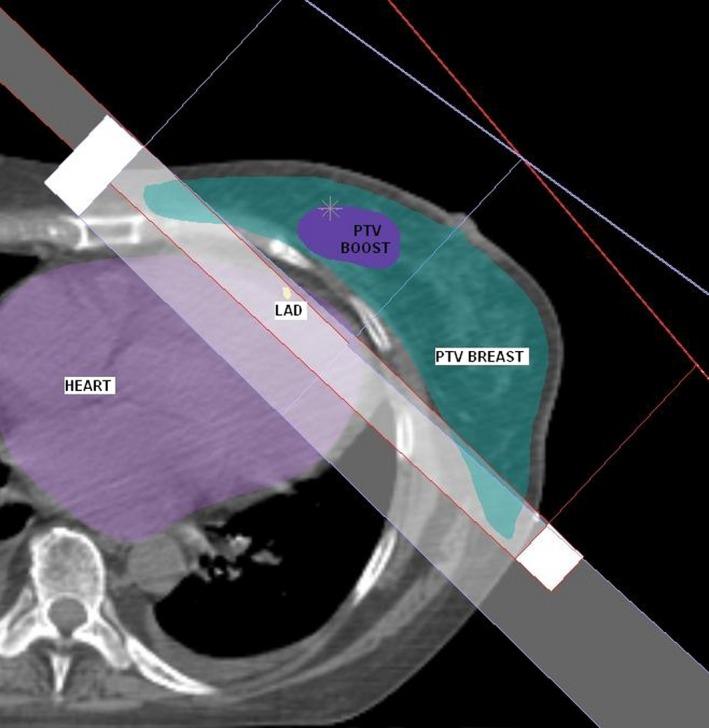

When irradiating the left breast, a small portion of the heart and left anterior descending coronary artery (LAD) are often included in the treatment field. Deep inspiration breath-hold (DIBH) techniques reduce dose to coronary structures, but are resource intensive and may not be tolerated by all patients. The aim of this study was to evaluate a simple multi-leaf collimator (MLC) modification technique with respect to target coverage and organ-at-risk sparing.

Forty nine patients with left-sided breast cancer, planned with a simultaneous integrated boost technique were retrospectively replanned with additional shielding of the LAD. Dose to the target volumes (whole breast and boost) and organs at risk (heart, ipsilateral lung and LAD) were assessed on both plans.